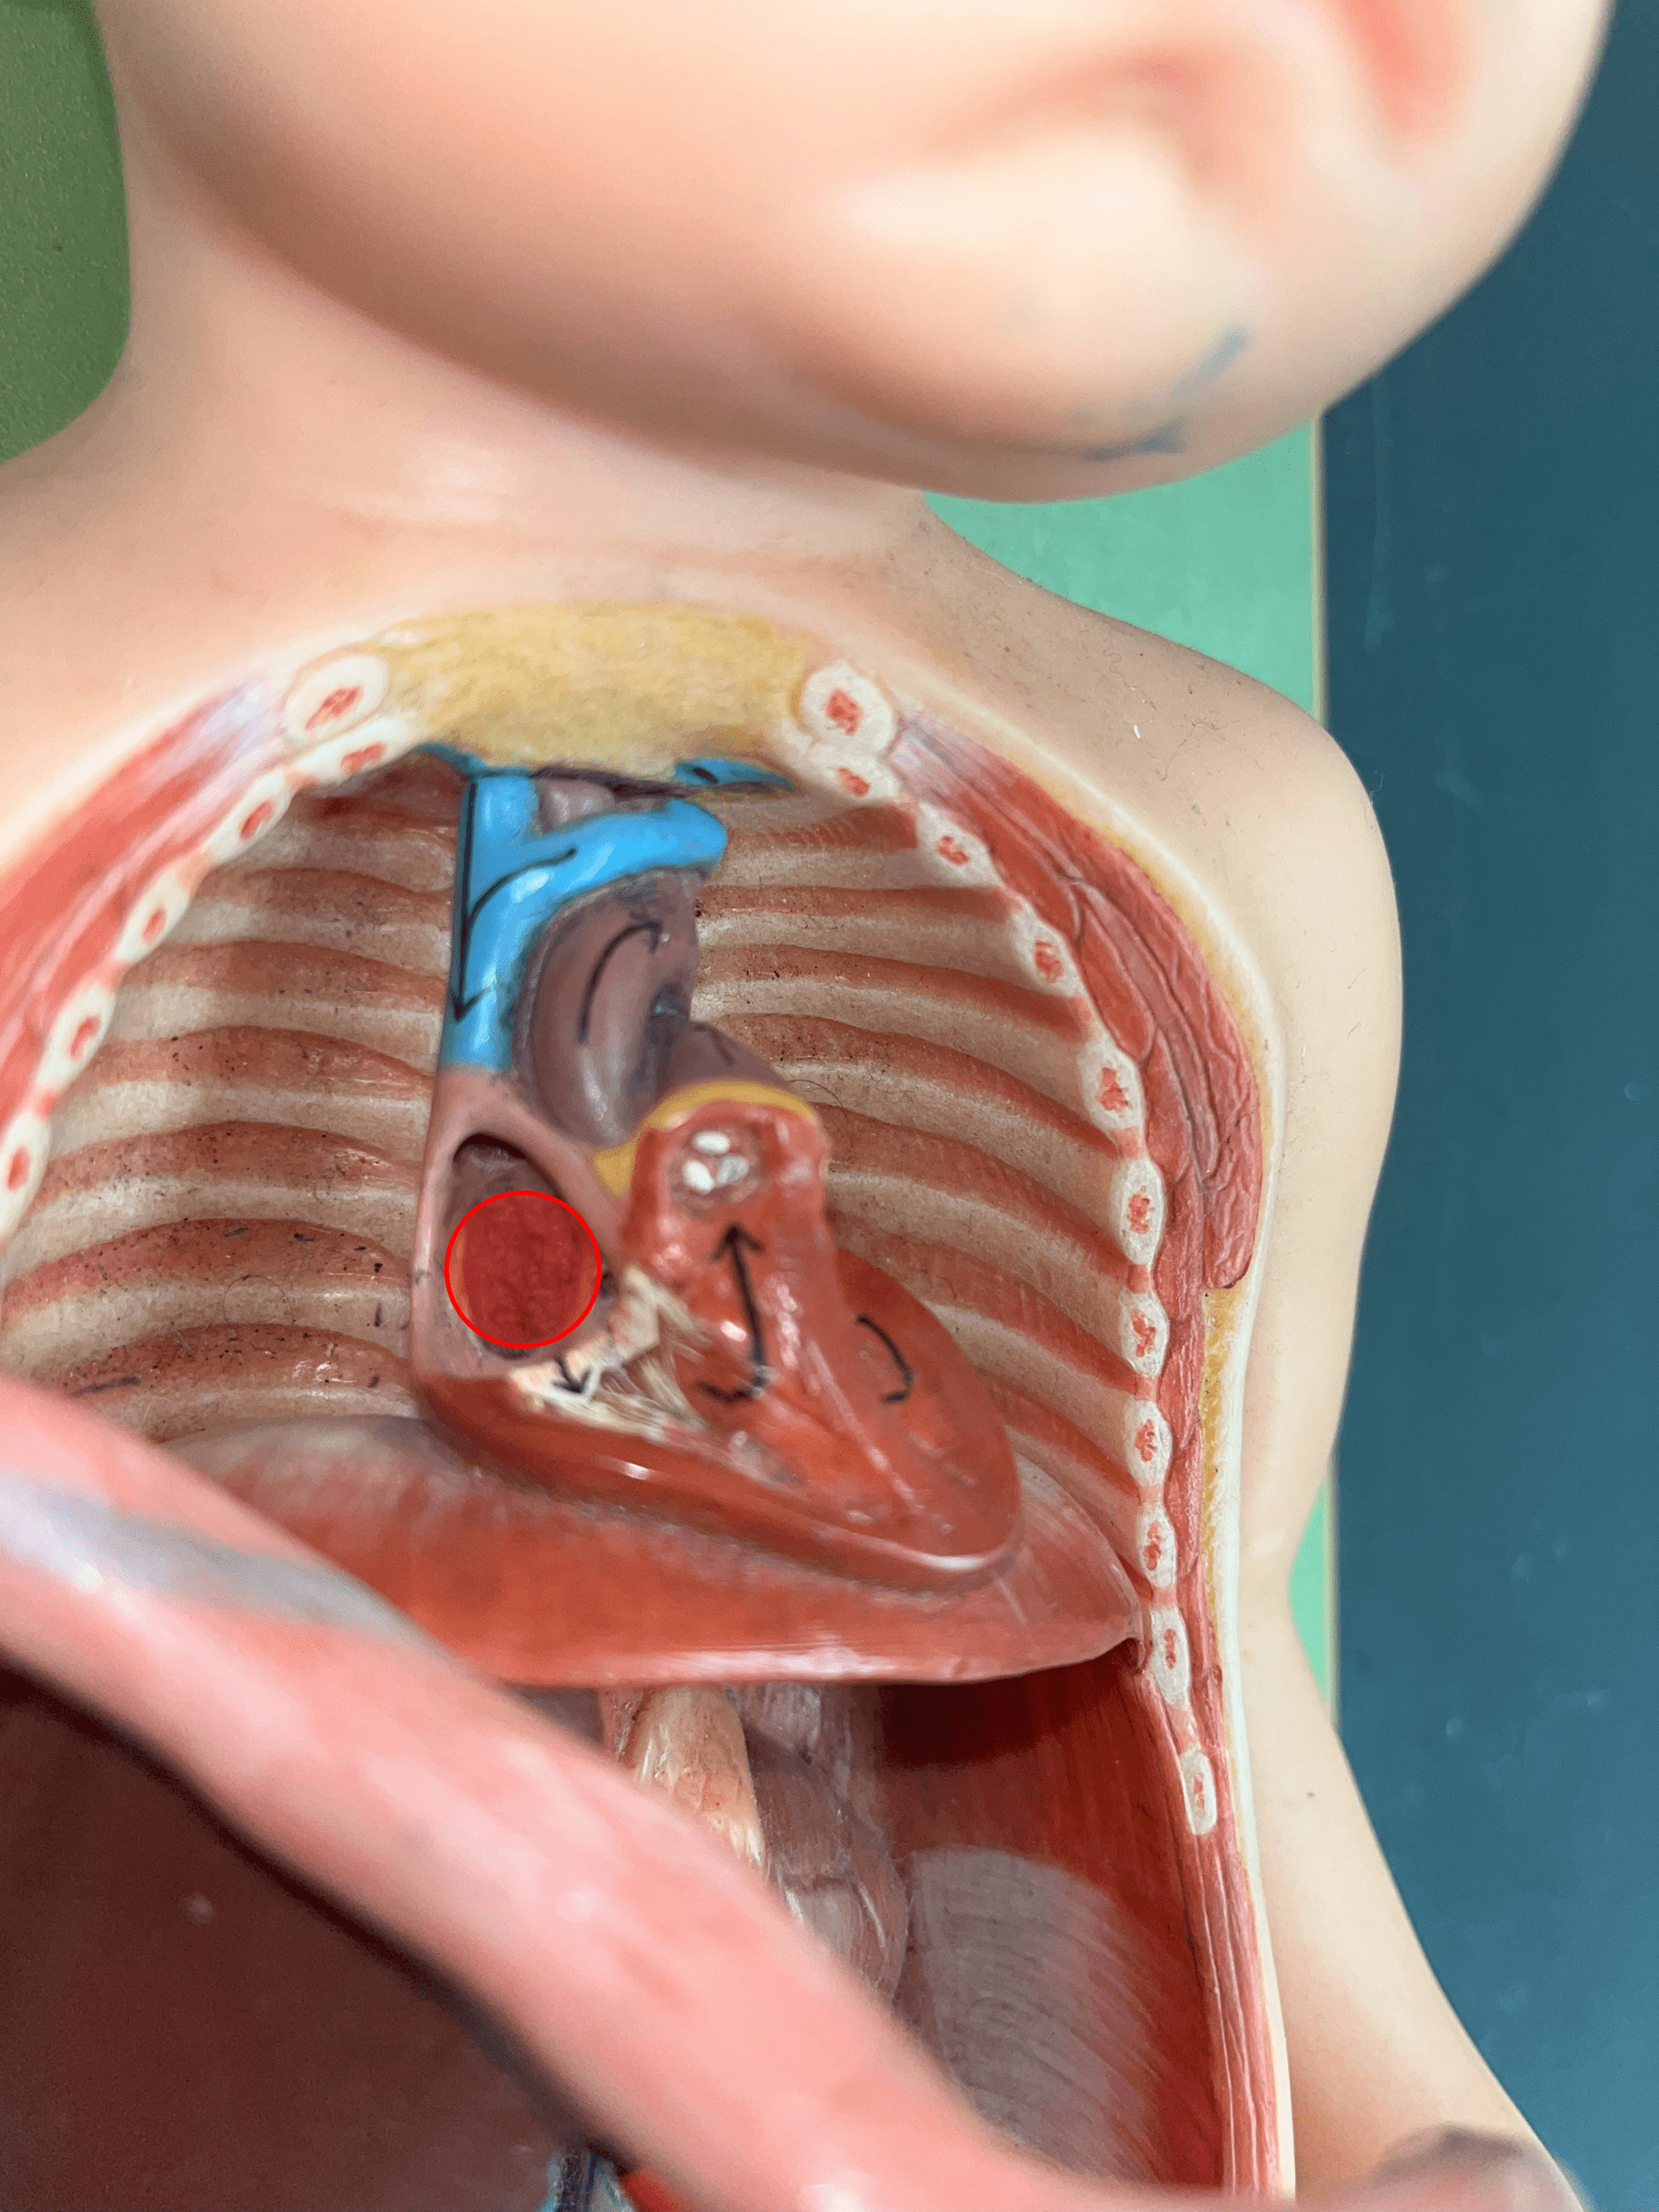

foramen ovale

• Part of the fetal circulation.

• Shortcuts blood to the right atrium from the left atrium, bypassing the pulmonary circuit.

• Becomes the fossa ovalis.

• Shortcuts blood to the right atrium from the left atrium, bypassing the pulmonary circuit.

• Becomes the fossa ovalis.